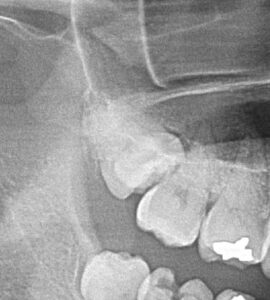

2つ目は水平埋伏智歯です。

歯冠部も歯根部もすべて下歯槽管に近接していて、骨や歯牙を削除するにも神経障害の危険性がありやっぱり大変でした。

ちなみに神経損傷なんてしていませんよ。